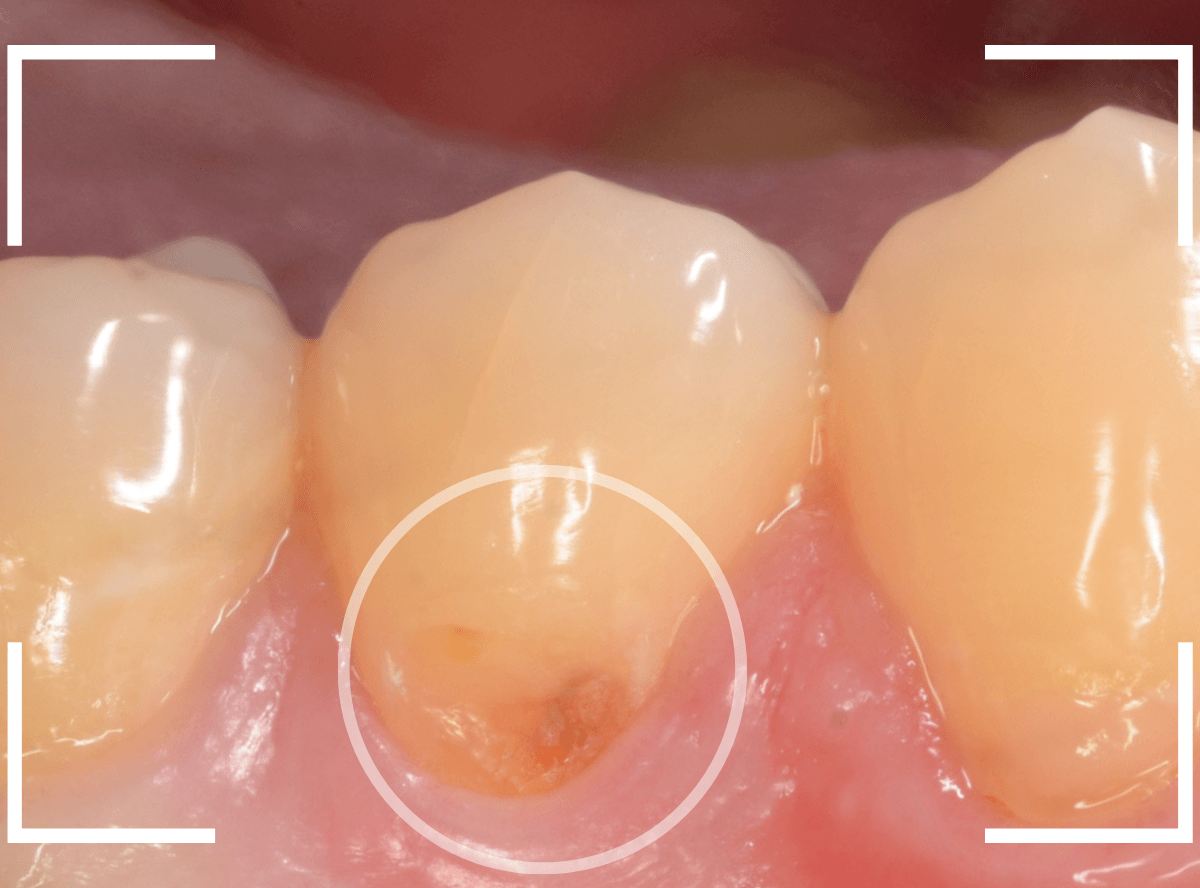

Case.3

「歯の側面が虫歯になってしみる」という訴えで来院された患者さんです。

これは、くさび状欠損といって、歯ブラシ圧の強すぎや歯ぎしりなどが原因で歯の側面が摩耗した状態の部分が若干の虫歯になった状態です。

くさび状欠損は、知覚過敏の原因になる事が多いですが、症状がなければ経過観察にする事も多いです。

今回は、表面が虫歯になっている事と、しみるという症状があるため、治療をする事になりました。

麻酔をして、虫歯の部分を除去します。

幸い、表面上の虫歯でしたので、歯の削除量は少なく済みました。

削った部分にレジンを充填して終わりです。

これでしみる症状は改善されると思いますが、麻酔をしているので、確認は次回来院時になります。